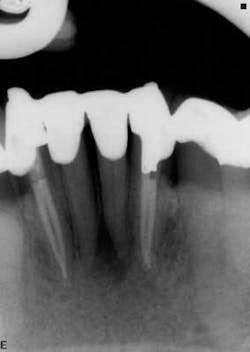

3. Molar teeth have more predictable canal anatomy.

Although there are exceptions to every rule and the potential for anatomic variability has to be considered in every tooth, for the most part molar teeth have consistent root canal anatomies. (12,15) There are well-documented cases of five and six or more canals in molar teeth, but these rare case reports are the exception more than the rule. (19,20) There has been increased awareness about the presence of a mid-mesial canal in mandibular molars over the last several years, and the use of cone beam computerized tomography has increased both our awareness and ability to locate this “extra” canal. (Figure 6) I consider all teeth that I treat to have one more canal than is expected, and so I am never surprised by what I find. If I access a mandibular molar with the expectation that four canals exist (and there could be a fifth or sixth), then the unexpected surprise occurs when only three canals are present. The vast majority of mandibular molars that I treat have four canals: two well-defined mesial canals that may or may not join in the apical one-third of the root and either two distinct canals or a dumbbell shape in the distal root. Because of the broad buccal-lingual dimension of the distal root, I almost always treat this root canal system as though it were two canals.

canal. Although molar teeth can and often do have variable

anatomy, most mandibular molars are going to have at least

three, and more commonly four canals.

in mandibular molars.